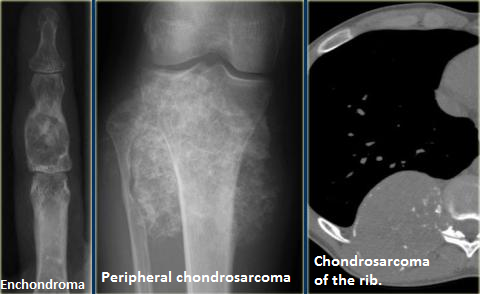

Matrice Chodnroide

- Rings and Arcs Calcifications

- Popcorn calcifications

- Correspond à des calcifications en périphérie des lobules hypodenses de cartilage